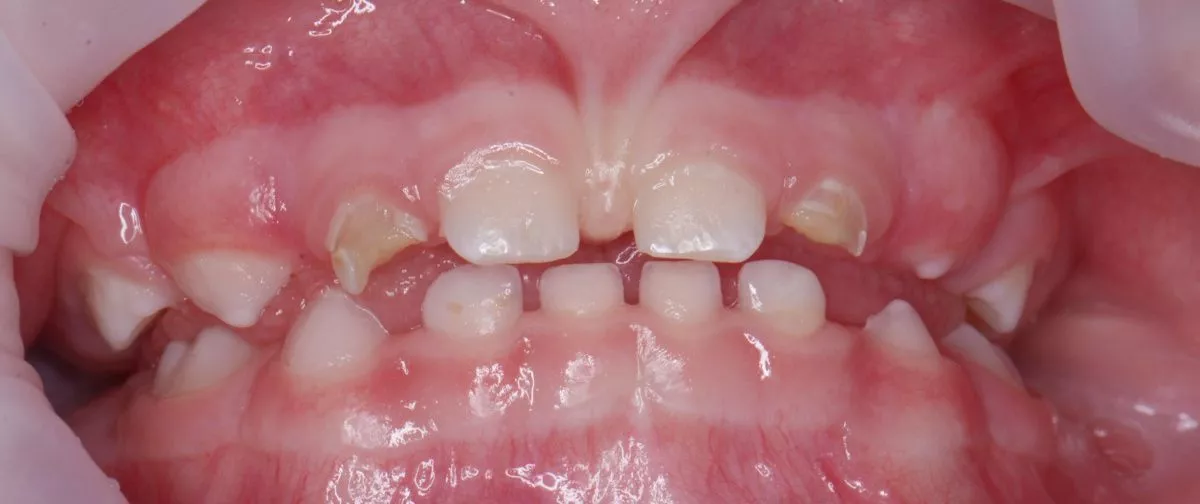

етская стоматология лечение под наркозом. Лечение под наркозом - установка коронок и профессиональная гигиена у детей - до процедуры

етская стоматология лечение под наркозом. Лечение под наркозом - установка коронок и профессиональная гигиена у детей - после процедуры